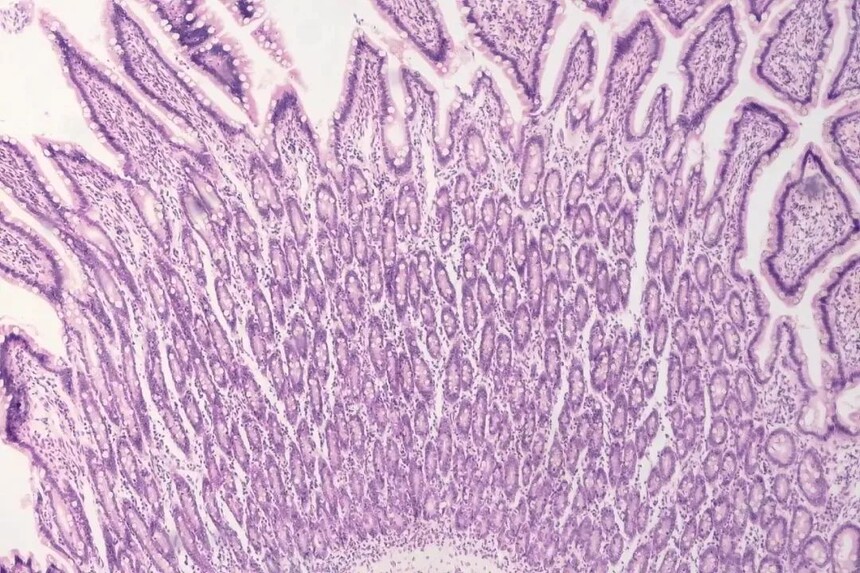

图像清晰,轻松捕获高清细节图像

U系列相机具备高灵敏度、高分辨率等性能特点每个像素都能够准确地捕捉并呈现实际场景中的细微特征从微小的零件到微观的纹理,所有的细节都非常清晰可辨。图像边缘和边界线条清晰,色彩饱满且准确。